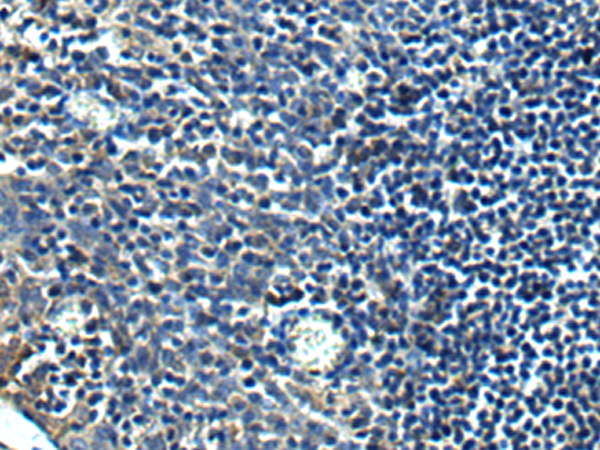

IHC positive control: |

Human tonsil |